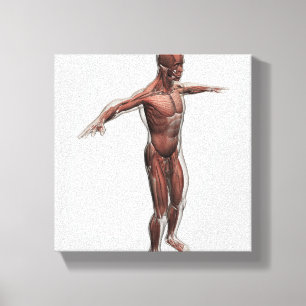

Lienzo Ilustracion médico del sistema muscular masculino

Precio 187,00 €